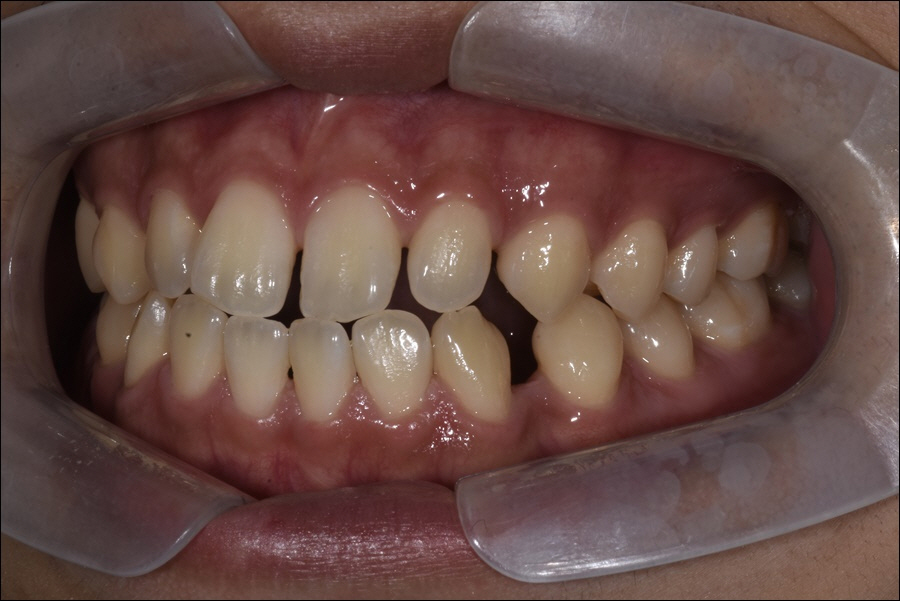

특히, 울퉁불퉁한 치열을 가진 분들이라면

정상적인 교합을 가지고 있는 분들 보다

더 잦은 내원으로 구강을 쾌적하게

관리받는 노력이 필요했어요.

before->after

가지런한 치열 보다 치아 사이에

음식물 찌꺼기가 낄 확률이 높았으며,

양치질을 하더라도 제대로 제거하기

쉽지 않기 때문이라 할 수 있었어요.

특히, 치아의 위, 아래 교합이 맞지

않는 분들은 저작 능력의 저하 뿐만

아니라 정확한 발음을 구사하기

어려웠기 때문에 다양한 기능적

불편함을 호소하곤 했어요.